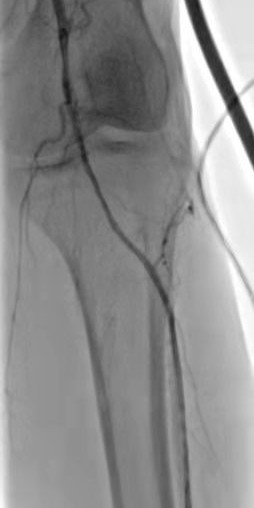

術(shù)后右下肢動(dòng)脈血流復(fù)通